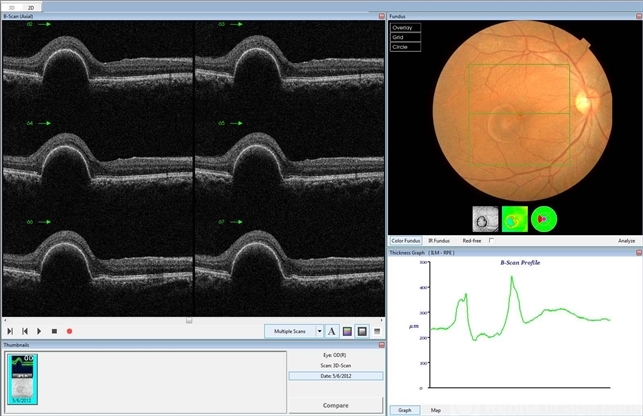

- pigment epithelial detachment (PED), optical coherence tomography (OCT), central serous chorioretinopathy (CSCR)

- OCT image of a 37-year-old man with a serous PED secondary to CSCR.